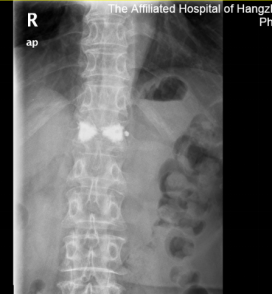

手术进行时:张大妈入院后进行了简单的术前检查,次日下午就在局麻下做了经皮穿刺球囊扩张椎体后凸成形术(PKP)。

30 分钟过后手术顺利完成,张大妈腰背疼痛症状明显好转。

次日,张大妈带着腰托就可以下地活动。术后第 2 天就顺利出院了。